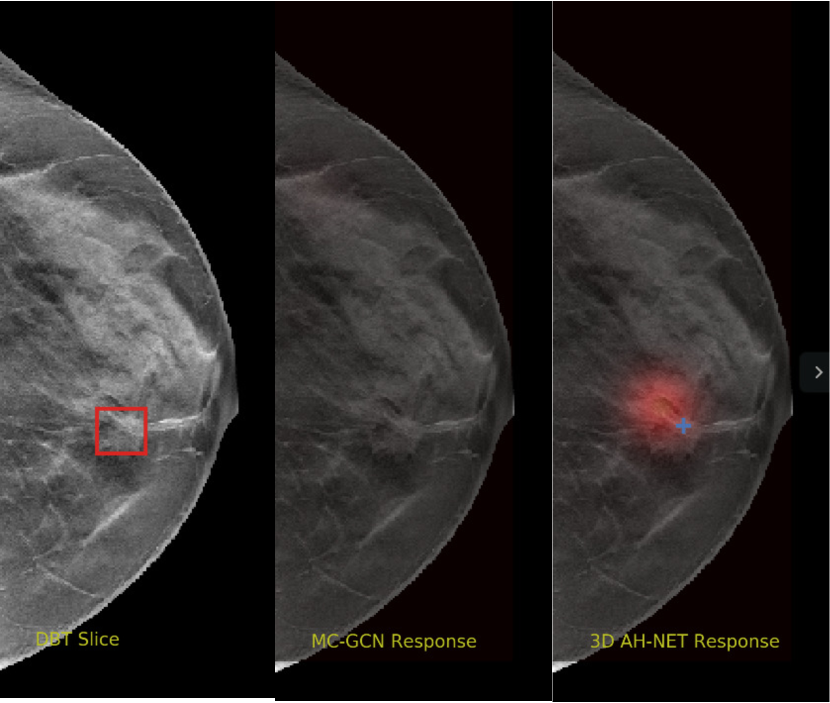

We selected some example slices from the DBT dataset to demonstrate the advantage of our proposed AH-Net for the Breast cancer screening. From Fig. 8 to Fig. 12, we show slices from five test DBT volumes that both the MC-GCN and the proposed 3D AH-Net could successfully detect the suspected breast lesion. The original DBT slice is shown on the left with the lesion annotated by our radiologist. Please note the original annotation is a 3D box. The figures in the middle and on the right are response maps from MC-GCN and 3D AH-Net overlaid on the original image, respectively. The detection locations obtained with non-maximal suppression are displayed with cross markers. As shown in the images, the proposed network can detect breast lesions varying in sizes and appearances. The confidence of the 3D AH-Net is usually higher than that of MC-GCN. From Fig. 13 to Fig. 17, we show five volumes that MC-GCN failed to detect the lesions since the lesions were not distinguishable from other breast tissues using the information within the slice. In contrast, 3D AH-Net was able to detect the lesions from such volumes using the 3D context between slices. As shown in Fig. 18 to Fig. 22, there are also volumes with lesions that both network failed to detect. Such lesions normally reside in the dense breast tissues. The boundary between these lesions and the normal breast tissues usually have low contrast. The networks sometimes also confuse them with other roundish structures in the breast such as lymph nodes or skin moles.

Figure 14: Example DBT slice 7 with a lesion that can only be detected by 3D AH-Net. The lesion is highly blended within the dense breast tissues which makes it challenging for both the radiologists and the networks to detect through a single slice. In contrast, the lesion can be detected by considering the consistency of the structure across a few neighbouring slices.

Refer to caption